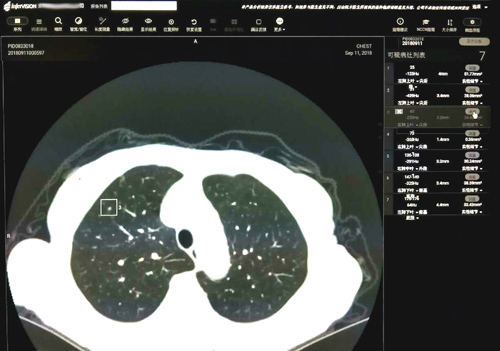

近期,临床医学院/附属医院放射科引进了九江市首套人工智能“InferRead CT Lung”肺部影像诊断辅助软件。该系统融合了大数据与人工智能等最新科技,可以帮助医生大幅度提高肺部结节筛查的效率与准确性。

这款由推想科技提供的软件结合临床医学院/附属医院最先进的 256排512层高端螺旋CT扫描的肺部图像,以其高性能的并行运算能力,通过测量CT值识别出实性、磨玻璃及钙化结节并同时显示所有结节的大小、体积。有了该软件的辅助,再小的结节也不易漏诊。影像科医生对检测的结节进行分析,反馈至软件中标记假阴性的结节和取消假阳性结节的标记。此外,它可通过对影像组学的自我深度学习,提高对图像全信息识别利用的诊断准确性;并且它的知识经验会随着病例增多不断自我优化,从而不断降低漏诊率、误诊率。